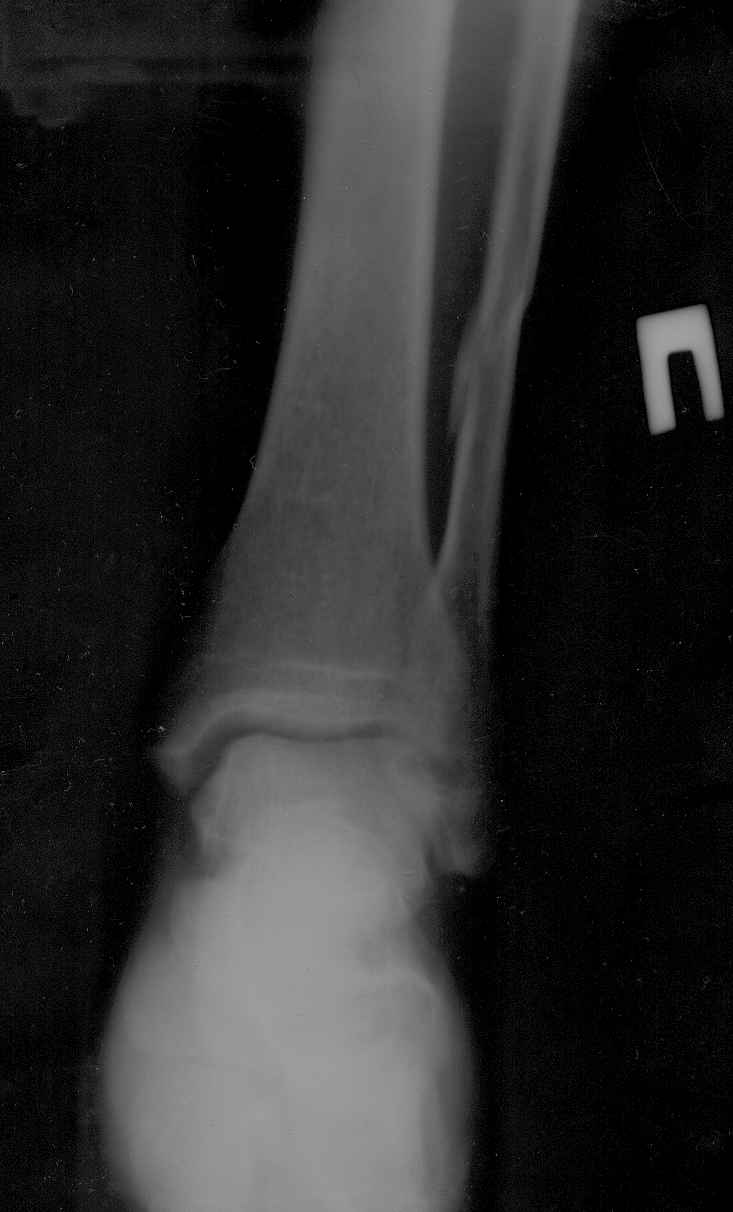

У пациента возраст 58лет закрытый перелом н/лодыжки почти без смещения и н/3 малоберцовой кости со смещением правой голени.

из сопутствующих-рассеяный склероз, ибс, гипертоническая болезнь. ro-снимки прилагаются. подскажите оптимальный метод лечения